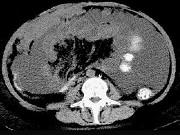

问题 男,51岁,直肠癌术后1年,腹胀,纳差,消瘦,影像检查如图,最可能的诊断是()

选项 A.直肠癌肝转移 B.直肠癌网膜转移 C.肝硬化腹水 D.术后改变 E.肠梗阻

答案 B